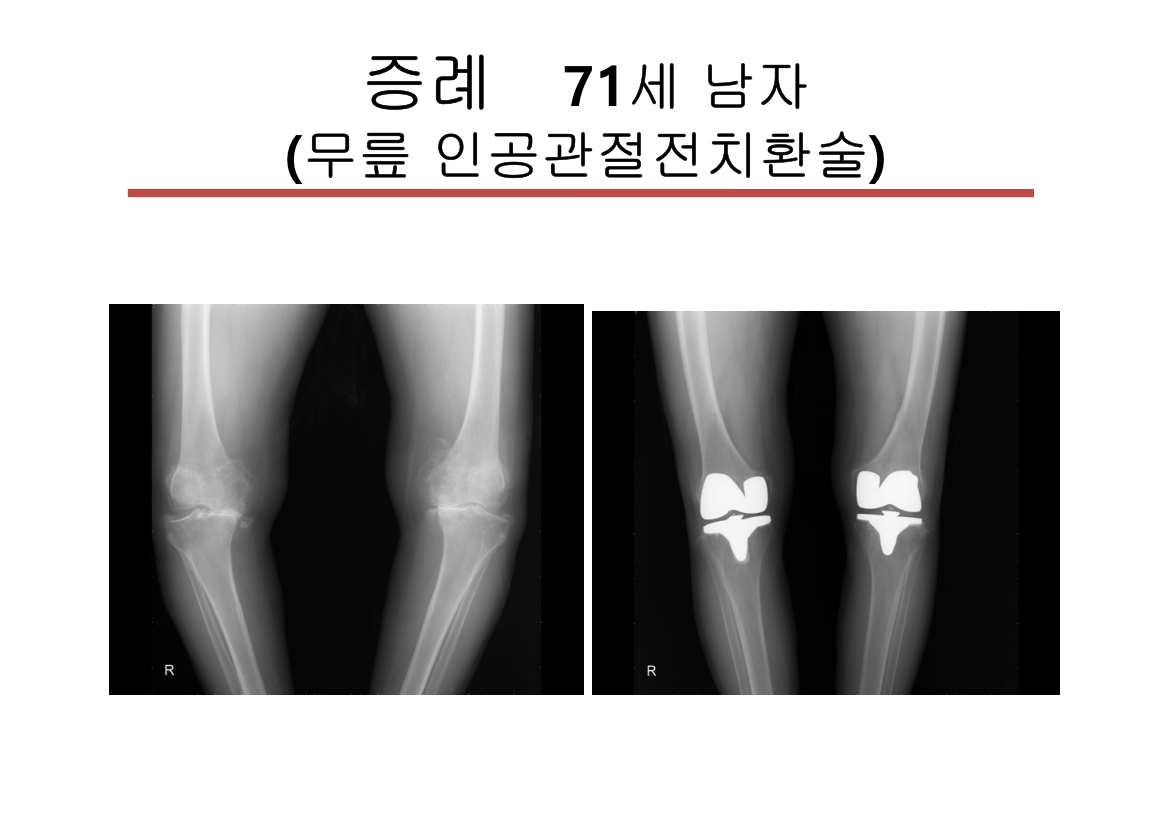

윤정로 병원장님 퇴행성 관절염 치료 자료

윤정로 병원장님의 퇴행성 관절염 치료 관련 자료 입니다.